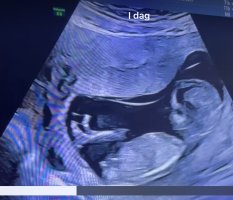

Spennende altså. Tror vi må få vite kjønn på ordinær UL for jeg klarer antageligvis ikke å vente, haha.Gutt?!

Men så ble jeg litt usikker med en gang jeg postet. Kanskje den er mer rett? Isåfall jente!Spennende altså. Tror vi må få vite kjønn på ordinær UL for jeg klarer antageligvis ikke å vente, haha.

Ja, jeg synes kanskje den er mer rett. Har sittet og studert videoklippet flere ganger nå og tenker den er mer i linje med ryggraden enn oppover. Kjempespennende uansett!Men så ble jeg litt usikker med en gang jeg postet. Kanskje den er mer rett? Isåfall jente!

Nå har vi fått vite kjønn, og det var det motsatte av det nub teorien viste meg. Haha!Ja, jeg synes kanskje den er mer rett. Har sittet og studert videoklippet flere ganger nå og tenker den er mer i linje med ryggraden enn oppover. Kjempespennende uansett!